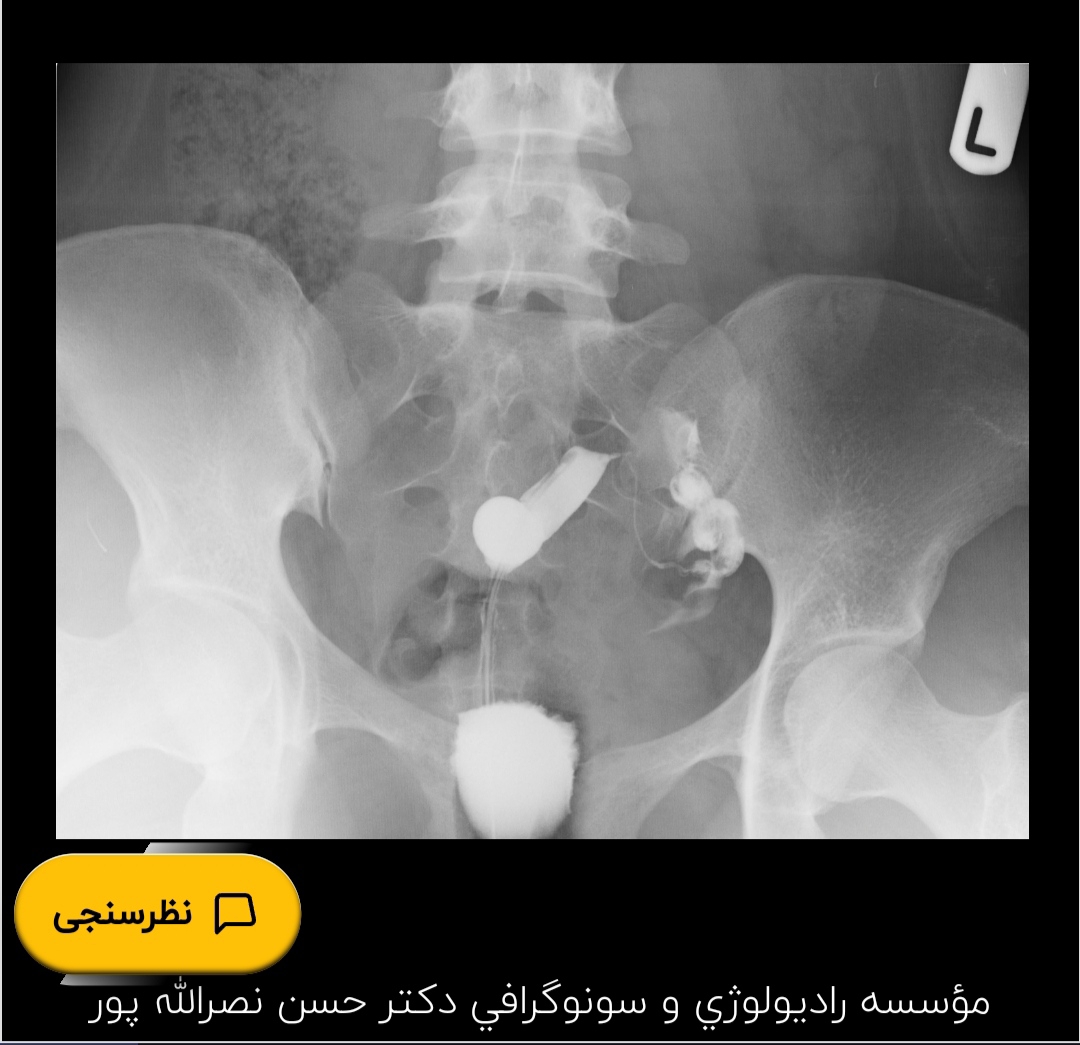

سلام خانم دکتر عزیز و اومایی های گل.من پنج ماهه اقدام به بارداری کردم و باردار نشدم الان عکس رنگی رحم انجام دادم و بهم گفتن ی لوله بیشتر ندارم آیا امکان بارداری طبیعی با ی لوله هست یا نه

تفسیر عکس رنگی رحم

یک لوله کامل مسدود شده

من اصلا ی لوله ندارم کلا

خانم دکتر آیا با این ی لوله و رحم تک شاخ بارداری طبیعی صورت میگیره یا باید از آی وی اف کمک بگیریم؟